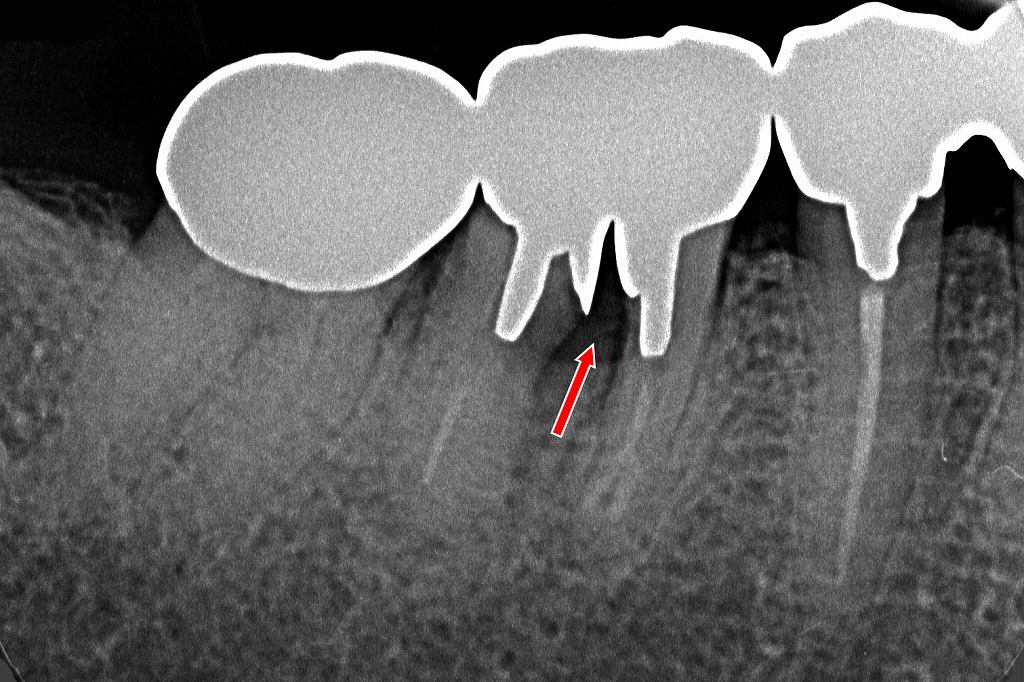

④ルートセパレーション歯に生じた遠心根の破折

赤矢印で示された部位は、分割された大臼歯の遠心根が破折している所見です。

● 遠心根の破折

今回のX線所見では、

遠心根に縦走する透過像が確認でき、遠心根の歯根破折が強く示唆されます。

破折により:

- 破折線に沿った透過像(黒く見える線)

- 周囲骨の吸収

- 根面の輪郭の乱れ

が生じ、補綴歯の維持力が失われています。

● 歯根破折が起きた背景

歯根分割後の根は、一般的に

- 支持骨量が限られる

- 応力集中が起こりやすい

- 咬合力が分散しにくい

といった理由から破折リスクが高くなります。

連結冠による補強を行っていても、遠心根は細く脆弱なことが多く、長期的には破折することがあります。